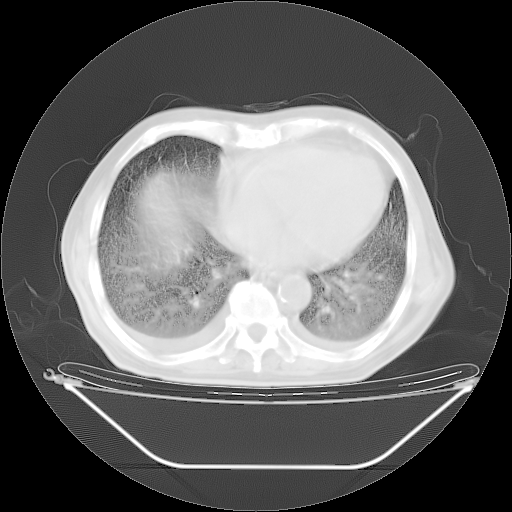

今天复查肺部CT,发现双肺广泛磨玻璃样改变。所以我把3月19日和5月9日相隔50天的肺部CT上传。请大家会诊。

2009年3月19日肺部CT片。

2009年3月19日肺部CT

5月9日肺部CT(在4月27日齐鲁医院肺部CT描述部分肺组织磨玻璃样改变,12天后肺组织广泛磨玻璃样改变)